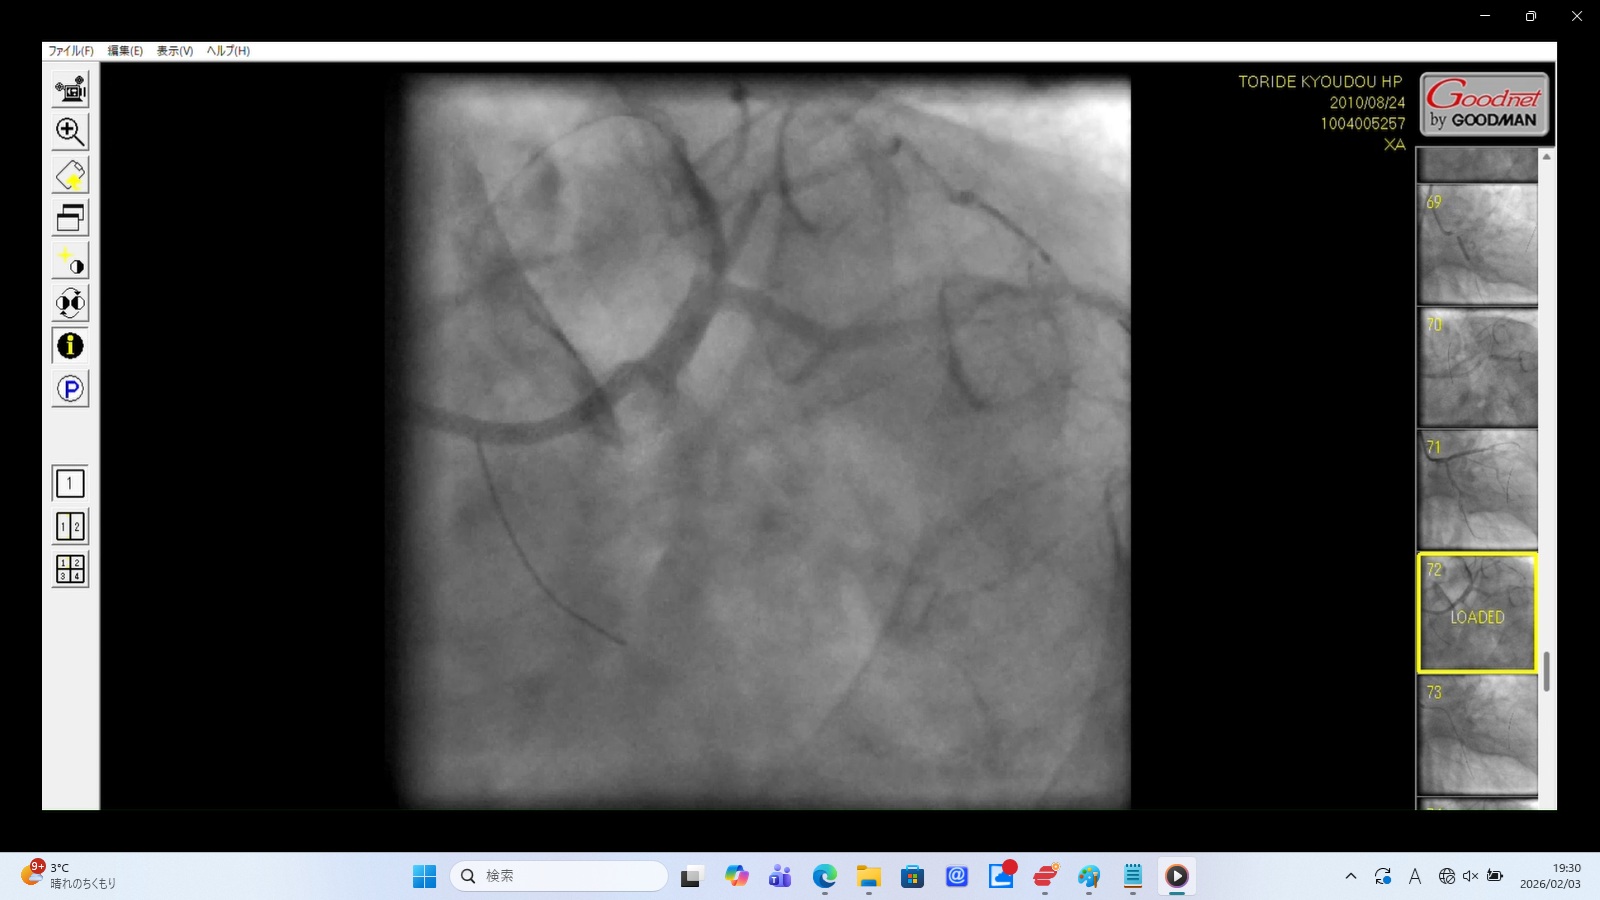

左前下行枝解離・穿孔、左冠動脈主幹部解離・損傷・完全閉塞、ステント様人工物の血管外脱落などの所見あり。 術者の岩井利之医師は「治療は成功した」と偽り、これらの大事故・大損傷を隠蔽した。救命のためには心臓血管外科での緊急手術が必要な状態であったはずだが、医師らはその手配をせず放置した。

左冠動脈前下行枝(LAD)のリアルタイム解離

左冠動脈主幹部解離(真腔と偽腔の併存)と血管外漏出

左冠動脈前下行枝(LAD)の穿孔

22時35分に開始され、右橈骨動脈にガイドワイヤーを挿入して手技が開始されたが、 冠動脈にアプローチできず、右大腿動脈から挿入された。その間、アプローチが失敗した時間帯のPCI画像が 存在せず、ここで大事故を起こした証拠であるこの間の画像が抜き取られた可能性が疑われる。 PCIは3時間と長時間を要し、その間の放射線被曝量も人体に深刻な影響を与えるほど大量であった。 PCIの動画を確認すると左冠動脈主幹部解離・損傷・閉塞、左冠動脈前下行枝解離・穿孔、 左回旋枝への血栓閉塞、ステント様人工物の血管外落下など多数の致命的な大事故が認められた。 救命のためには心臓血管外科での開胸手術が必要のはずであったが、PCI終了後、医師は遺族に対して「治療は無事成功した」としてこの大事故を隠蔽し、心臓血管外科への手配をせずに放置し談笑していた。